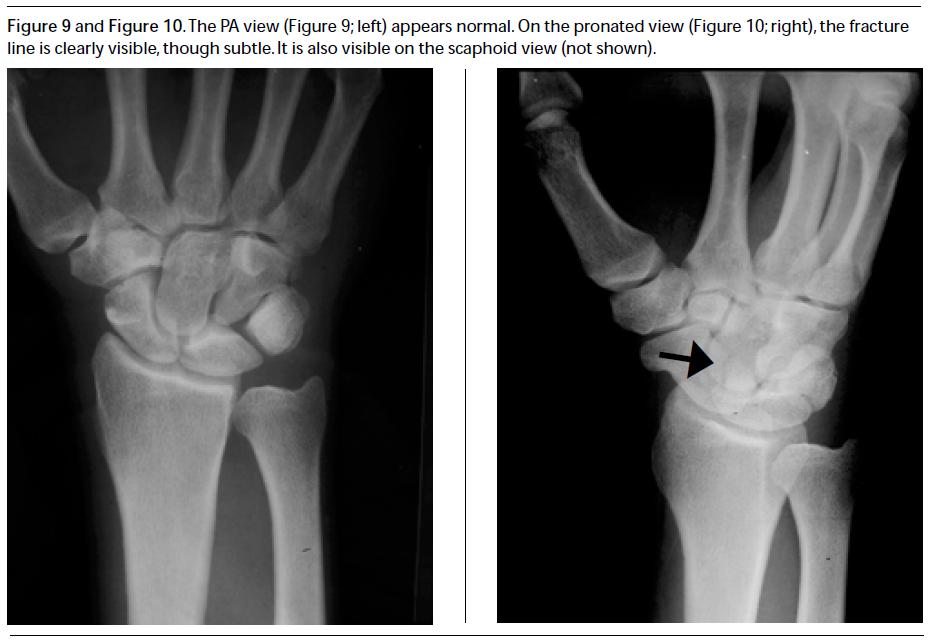

Scaphoid view radiograph of the left wrist The BMJ